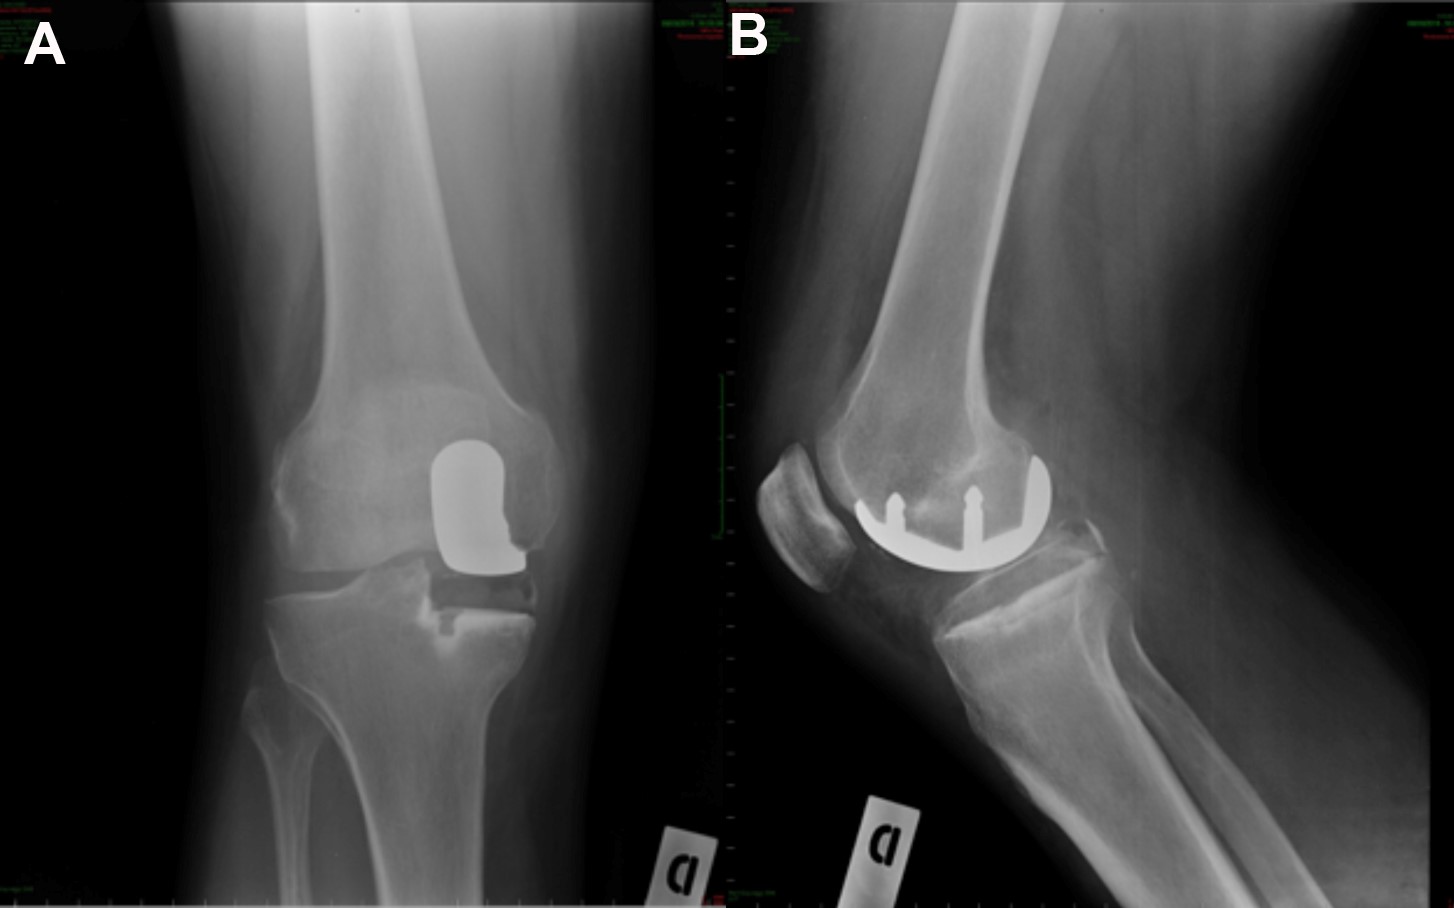

Nella protesi totale del ginocchio (Fig. 4 e 5) vengono sostituite con parti metalliche le superfici di cartilagine danneggiate e una piccola quantità di osso sottostante alle estremità del femore e della tibia di tutto il ginocchio. Le parti metalliche generalmente vengono cementate all'osso con uno speciale cemento. Un inserto di plastica speciale molto resistente viene inserito tra le componenti metalliche per creare una superficie di scorrimento liscia. La superficie inferiore della rotula viene tagliata e sostituita con un bottone di plastica che viene anch’esso cementato. Alcuni chirurghi non protesizzano la rotula o lo fanno a seconda del caso, altri (come noi) la protesizzano sempre: non vi è evidenza scientifica in letteratura che dimostri la superiorità di una scelta rispetto all'altra quindi la scelta di protesizzare la rotula o meno dipenderà essenzialmente dall'esperienza del singolo Chirurgo.

Nella protesi monocompartimentale del ginocchio (Fig. 5 e 6) vengono sostituite con parti metalliche le superfici di cartilagine danneggiate e una piccola quantità di osso sottostante alle estremità del femore e della tibia solo di un compartimento (mediale o laterale) del ginocchio. I legamenti del ginocchio non vengono sacrificati. Questa protesi è meno invasiva di quella totale (4), consente un recupero più veloce ma può essere utilizzata solo nei casi in cui l’artrosi non coinvolga gli altri compartimenti del ginocchio (compartimento contro-laterale e/o femoro rotuleo). Esistono anche protesi monocompartimentali di femoro-rotulea: queste vengono utilizzate in casi selezionati di artrosi a carico di questo compartimento.